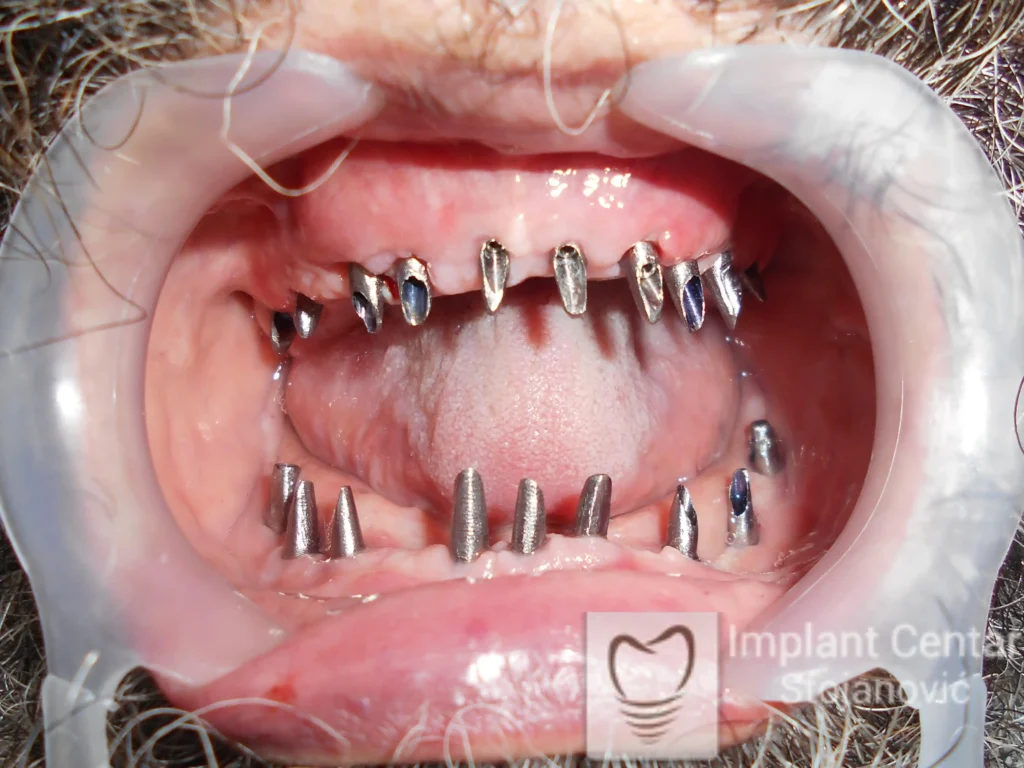

Nakon vađenja zuba, ugrađeni su implantati. Na slici 3 prikazan je ortopan snimak sa ugrđenim implantatima. Tokom perioda osteointegracije, pacijent je bio zbrinut fiksnim privremenim krunicama na implantatima, koje su izrađene samo dva dana nakon hirurške intervencije.